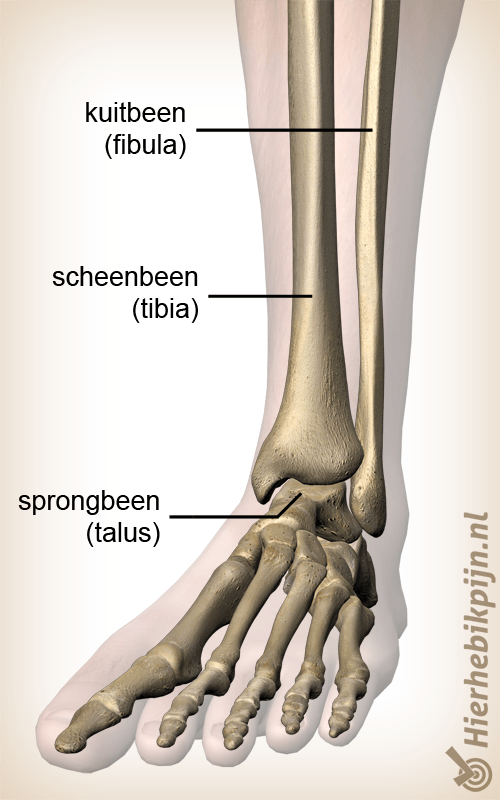

Enkel